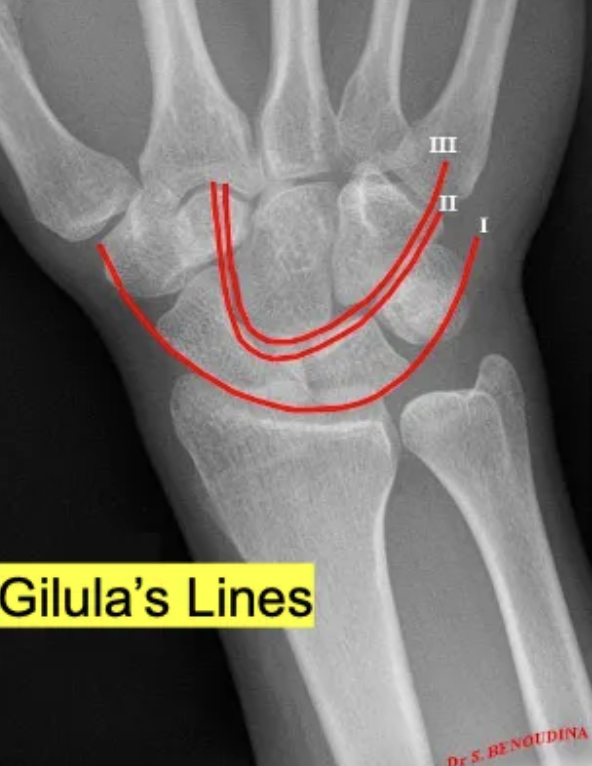

What are the 3 important lines in hand XR?

A

GILULA’S LINES

1. Proximal aspect of proximal carpal row

2. Distal aspect of proximal carpal row

3. Proximal aspect of distal carpal row